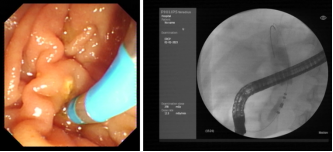

首例手术患者为一例局部晚期胰腺癌病人,失去了根治性手术的机会,同时因梗阻性黄疸且伴有糖尿病等基础疾病,一般状况较差,难以耐受化疗,常规治疗手段无法有效开展。针对该患者的病情特点,西安交通大学副校长吕毅教授、一附院肝胆外科仵正主任、胆胰内镜外科孙昊主任、胰腺外科王铮主任等经过仔细充分的术前讨论,与患者家属进行了多次医患沟通,最终决定为该患者实施内镜下脉冲电场肿瘤消融术。经过充分的术前准备,在医院麻醉手术部、介入手术室等团队的支持配合下,由肝胆外科孙昊主任医师、杨雪副主任医师、李宇主治医师、任冯刚博士等为该患者成功实施了ERCP+内镜下脉冲电场肿瘤消融术+胆道支架植入术。得益于脉冲电场能量高度密集的特点,脉冲消融过程仅用时约100秒,消融区平均温度40℃,手术过程安全可控,术后患者生命体征平稳,胆汁引流通畅,恢复顺利。2月8日,患者顺利出院,患者家属向医疗团队献上锦旗,表达真诚的谢意。患者家属眼含热泪地说到:“非常感谢交大一附院的医生护士,患者刚开始状态很差,通过这次手术,患者吃饭、精神都比以前好了很多,给我们带来了希望。”

本次手术采用了具有完全自主知识产权的国产高性能医疗器械。脉冲电场消融导管为吕毅教授团队自主研发、通过脉凝医疗实施转化的EndoPulse HPB阵列式脉冲电场消融导管,该导管头端由多支环形电极构成阵列,可以满足不同类型病变的应用需求。脉冲电场能量平台为赛诺微医疗科技与吕毅教授团队合作研发的Dophi®陡脉冲治疗仪。